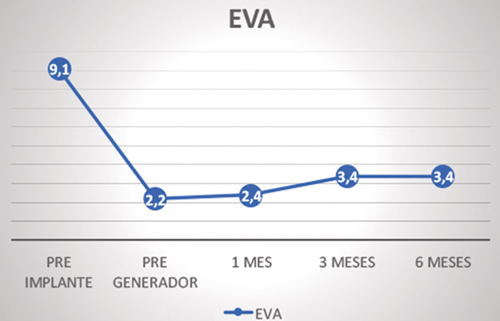

La intensidad del dolor medida en la escala visual analógica (EVA) respecto a la situación basal (9,0 ± 1,3) mostró una disminución estadísticamente significativa (p < 0,001) a las 2 semanas (2,3 ± 2,2), 1 mes (2,4 ± 2,4), 3 meses (2,7 ± 2,1) y 6 meses (3,4 ± 2,4) (Figura 2).

Fig. 2. Evolución de la intensidad del dolor según la EVA

La intensidad del dolor en la EVA pasó de 9,1 antes del implante a 3,4 a los 6 meses, lo cual supone una mejoría del 63 %, con una caída mínima a lo largo de los meses. El porcentaje de mejoría subjetiva a los 6 meses fue del 70,6 %. Un indicador de la mejoría obtenida es la mencionada disminución o cese en la ingesta de fármacos analgésicos. Otro dato llamativo es el caso del paciente afecto de síndrome del túnel de tarso, el cual con solo 39 años estaba en lista de espera quirúrgica para la amputación del pie, por la imposibilidad de aguantar el dolor, y sin embargo en la actualidad lleva una vida prácticamente normal, deambulando con leve limitación.